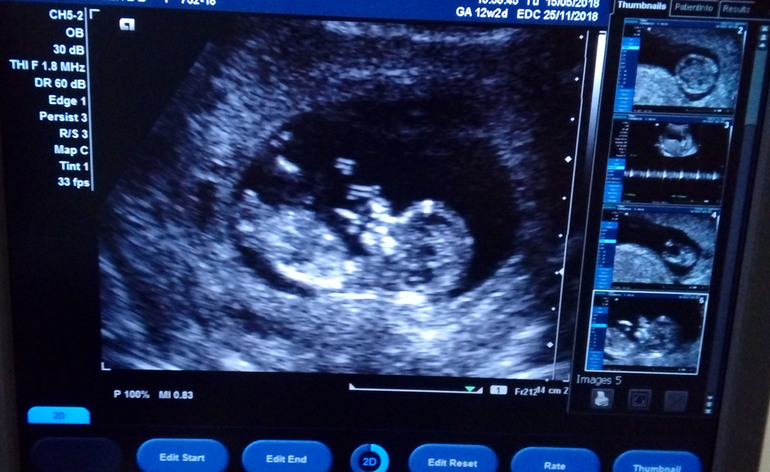

Срок по месячным 12 недель и 2 дня, по узи 12 недель и 6 дней. Все параметры в норме, врач сказала, что хороший малыш, правда соня. Пыталась растормошить - не вышло. Включила послушать сердцебиение и разрешила сделать фотографию малявки на телефон. Предположила пол, но закрашивать кружочек пока не буду. Мало ли, это ведь еще не точно.

Фото заключения и малыша прилагаю.